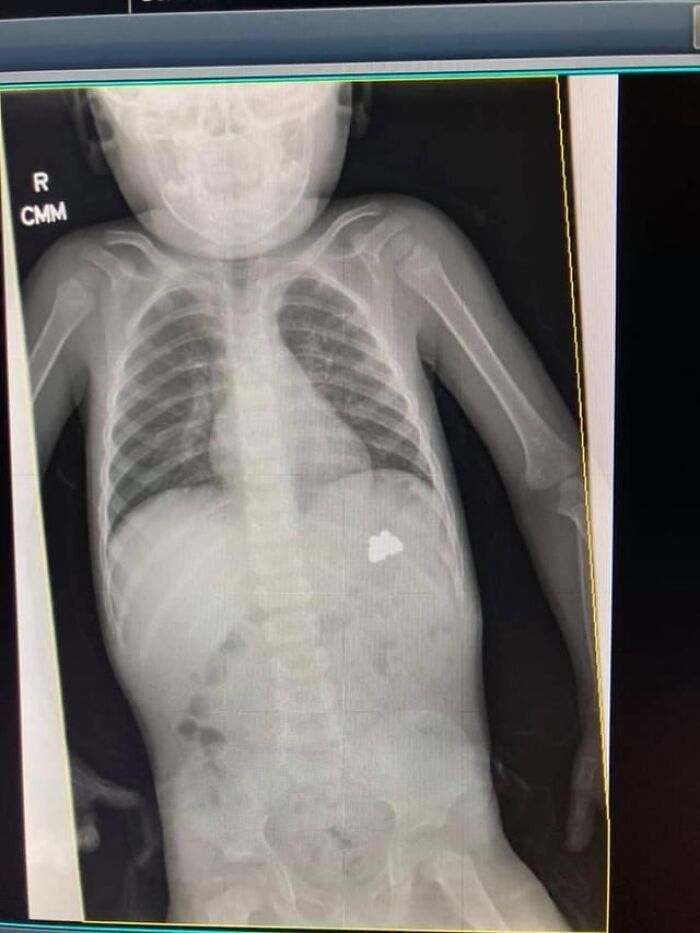

#25 My 9 Year Old Daughter Broke Her Arm. The Doctor Said She Will Heal Fine. Should I Get A Second Opinion?

Image credits: medical